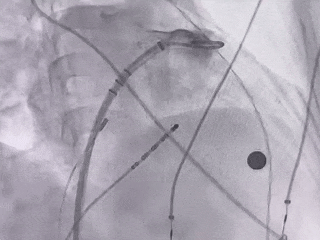

术中DSA肝位造影:双分叶鸡翅型左心耳

肝位造影,心房侧显影,轴向偏前,下缘早分叶

开口23.5mm,深度18.1mm

封堵前多角度进行造影确认缺损

肝位造影

右肩位造影